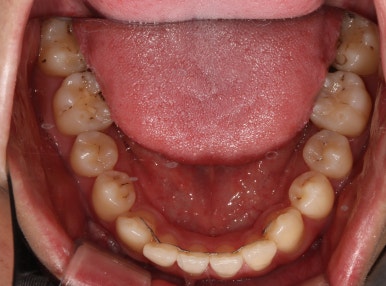

충치가 많은 것 같아요. 치료할 것은 다 치료받고 싶어요.

얼마 전에 저희 병원에 왔던 환자입니다.

어머니는 우리 병원을 오래 다녔던 환자분. 저희 치과를 믿고 방문해 주셨습니다.

충치는 몇 개 일까요?

맞아요. 충치는 대체 몇 개 일까요?

까맣게 보이는건 다 치료해야할까요?

얼마나 어떻게 치료할진 누가 결정하는 걸까요???

저 뿐만 아니라 우리 모두 까만색이 몇 갠지는 셀 수 있으니까,

제가 세보니깐 총 17개였습니다.

그럼 총 치아가 28개인데 17개가 썩었으니... 약 60%정도가 충치라는 얘기네요...